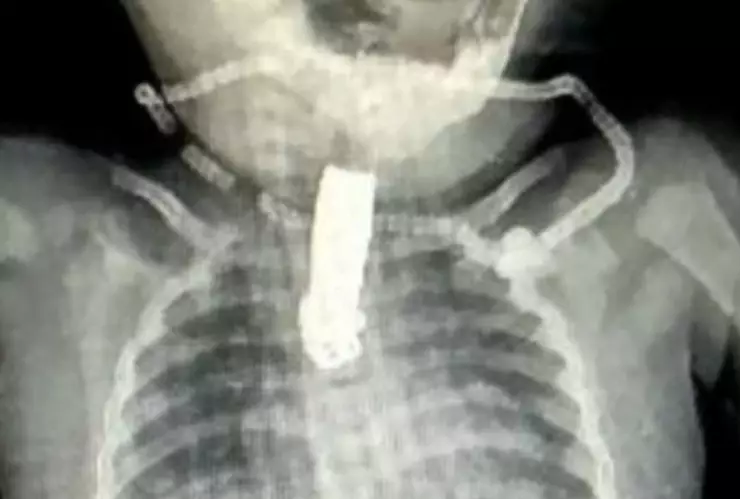

Así que se fueron al hospital más cercano a su vivienda en el distrito de Nashik en la India para que los médicos atendieran a su bebé, una niña de 8 meses. Ahí le tomaron una radiografía para empezar a atender su salud.

De esa forma se dieron cuenta que la niña se había tragado un filoso cortauñas. De inmediato la bebé fue sometida a cirugía que duró más de una hora en el Colegio Médico Dr. Vasantrao Pawar en Adgaon.